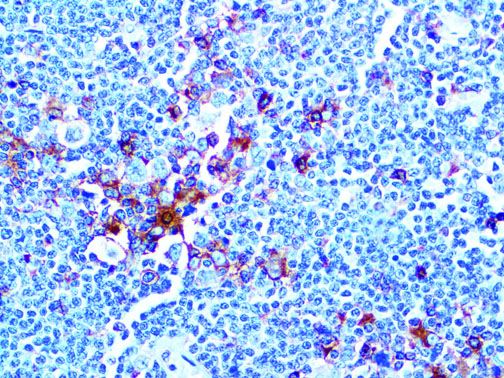

Clinical and laboratory manifestations of HLH include fever, enlarged liver and/or spleen, neurologic dysfunction, coagulopathy, liver dysfunction, cytopenias (i.e., low levels of erythrocytes, leukocytes, and/or platelets), hypertriglyceridemia, hyperferritinemia, hemophagocytosis, and eventually diminished NK cell activity as the immune system becomes progressively paralyzed. HLH can be familial (primary HLH) or secondary to another disease process (sHLH), such as rheumatic disease, in which it is referred to as macrophage activation syndrome (MAS, characterized by elevated ferritin).